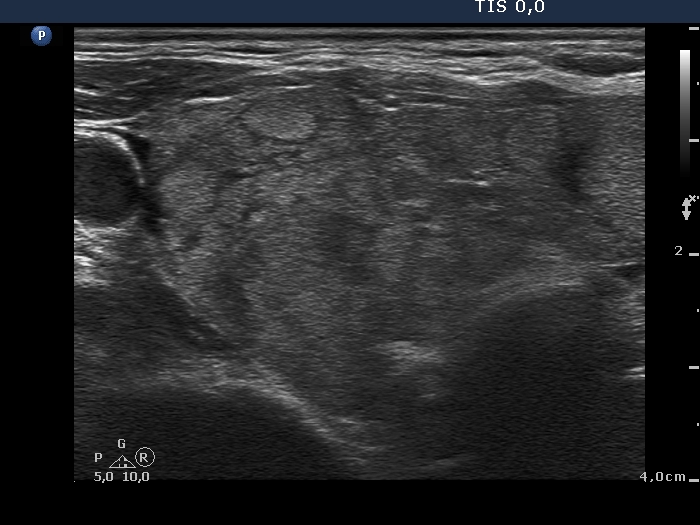

First examination (first row of images):

Clinical data: A 75-year-old woman was referred for evaluation of a goiter which was palpated by her GP.

Palpation: Both lobes were a bit firm and enlarged. There was a firm nodule in the isthmus.

Laboratory tests: TSH 4.49 mIU/L, aTPO 40 U/mL.

Ultrasonography. The thyroid was echonormal and had numerous discrete echonormal lesions. The largest of them was located in the isthmus. None of the lesions shared oncological importance.

Cytology was performed form the lesion in the isthmus and resulted in lymphocytic thyroiditis.

Suggestion: TSH and ultrasound in a year.